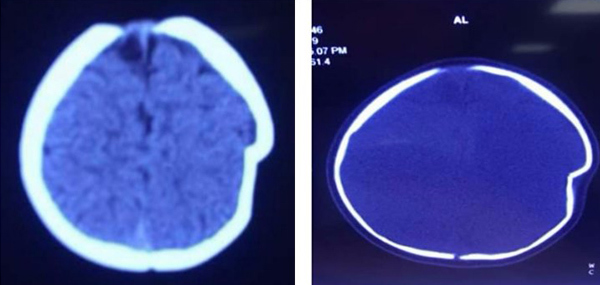

| Sọ bé gái bị lún sâu 1 cm sau cú ngã từ độ cao 1 m |

BS Hà Xuân Tài, Phó khoa Ngoại thần kinh, BV đa khoa tỉnh Phú Thọ cho biết, bé bị lún sọ thái dương đỉnh trái, do lún sâu nên các bác sĩ đã phải phẫu thuật nâng xương. Sau mổ 1 tuần, sức khoẻ bệnh nhi đã ổn định và được xuất viện.

Theo BS Tài, lún sọ pingpong thường gặp ở trẻ nhũ nhi dưới 1 tuổi. Nguyên nhân thường do tai biến sinh có thủ thuật, hay trẻ bị ngã khi tập đứng, tập đi và trẻ bị ngã ở độ cao thấp. Vị trí lún thường gặp là vùng đỉnh hộp sọ.

Do ở trẻ nhũ nhi hộp sọ có khả năng tự điều chỉnh tốt nên hiếm khi phải mổ cấp cứu ngay, trừ những trường hợp lún sọ mức độ nhiều, tổn thương rách màng cứng và tổn thương não.